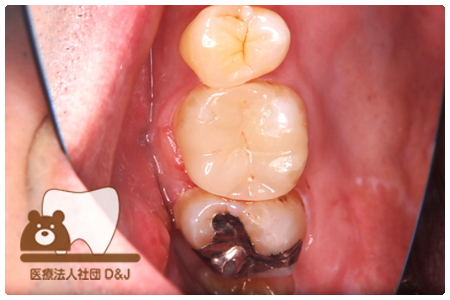

症例8フルジルコニアクラウン

治療前

治療中

治療後

29歳 女性

- 治療内容

- 銀歯からフルジルコニアクラウンへの修復

- 治療期間

- 根の治療含め3か月

- 費用

- 自費

フルジルコニアクラウン:77,000円(税込)

- その他の治療の費用は含まれておりません。

- リスク・副作用

- 強い衝撃が加わると欠けたり割れたりする可能性があります。また、噛み合わせの状態によっては脱離や周囲の歯への影響が出ることもあります。